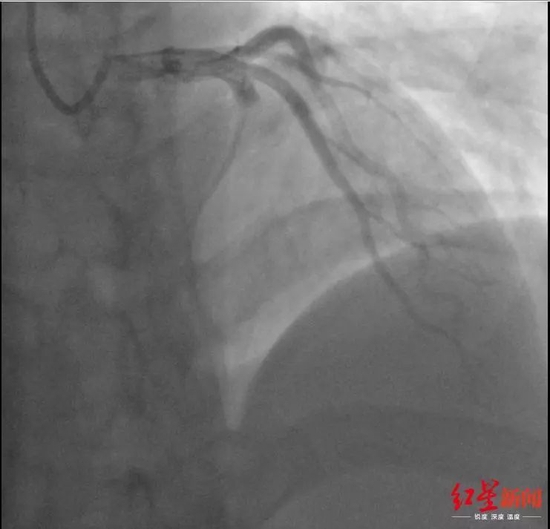

小蒲术前的冠脉造影显示 前降支血管严重堵塞

1个小时后,手术完成,小蒲的冠脉血流恢复情况良好。问诊中,医生了解到,小蒲虽然没有高血压、糖尿病、心梗家族病史,但偶尔会抽烟,身高175厘米、体重100公斤的小蒲经常熬夜打游戏,却不爱运动,同时,小蒲血脂指标超高,但此前一直都不知道。